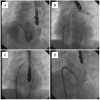

The basic steps of muscular device implantation have been described in the literature [31, 32, 33, 34, 35, 36] and consist of the following: the VSD is crossed from the left side, by using a Judkins right, AL1 or Cobra catheter and a soft Glidewire (0.035”, J tip; Terumo Corp., Tokyo, Japan); the wire is advanced to pulmonary artery, where it is snared with a Gooseneck snare (Microvena Corporation, St Paul, MN, USA; 20-25 mm in adults, 10-15 mm in children) ( Figure 2), and exteriorised out of the right internal jugular vein or femoral vein establishing an arteriovenous circuit. In order to obtain the straightest course of the delivery system, the right internal jugular vein is chosen for mid-muscular or apical defects, and the femoral vein for muscular defects located more anteriorly. Over the circuit, an appropriate size of delivery sheath is advanced from the vein all the way until the tip of the sheath is in the ascending aorta. The dilator is withdrawn and the sheath is pulled back in the left ventricle.

When the tip of the sheath is placed in the mid cavity of the left ventricle, the dilator and the wire are gently removed. A left ventriculogram is usually repeated to confirm the position of the long sheath and also to obtain additional information about the position and the size of the VSD. Using both angiographic and echocardiographic data a muscular VSD occluder 1 to 2 mm larger than the maximum size of the defect is chosen; the device is attached to the delivery cable, loaded into the plastic loader, introduced and advanced into the sheath. The left disc is deployed in the left ventricular cavity, making sure it does not impinge on the mitral valve apparatus. The entire system is then withdrawn towards the septum, and the central waist and the proximal disc are deployed. A test angiogram is done to verify the correct position of the device: an echocardiographic view is also very important to confirm the position of the two discs on the left and right sides of the septum respectively, and of the central waist within the muscular septum. The device is then released ( Figure 3). A final angiogram is performed approximately 15-20 minutes afterwards to assess the position of the device and possible residual shunt. Patients receive aspirin (2-5 mg/kg/daily maximum 300 mg/daily) for 6 months and are asked to follow a strict regime of endocarditis prophylaxis.

A similar approach may be used to close multiple muscular VSDs ( Figure 4).